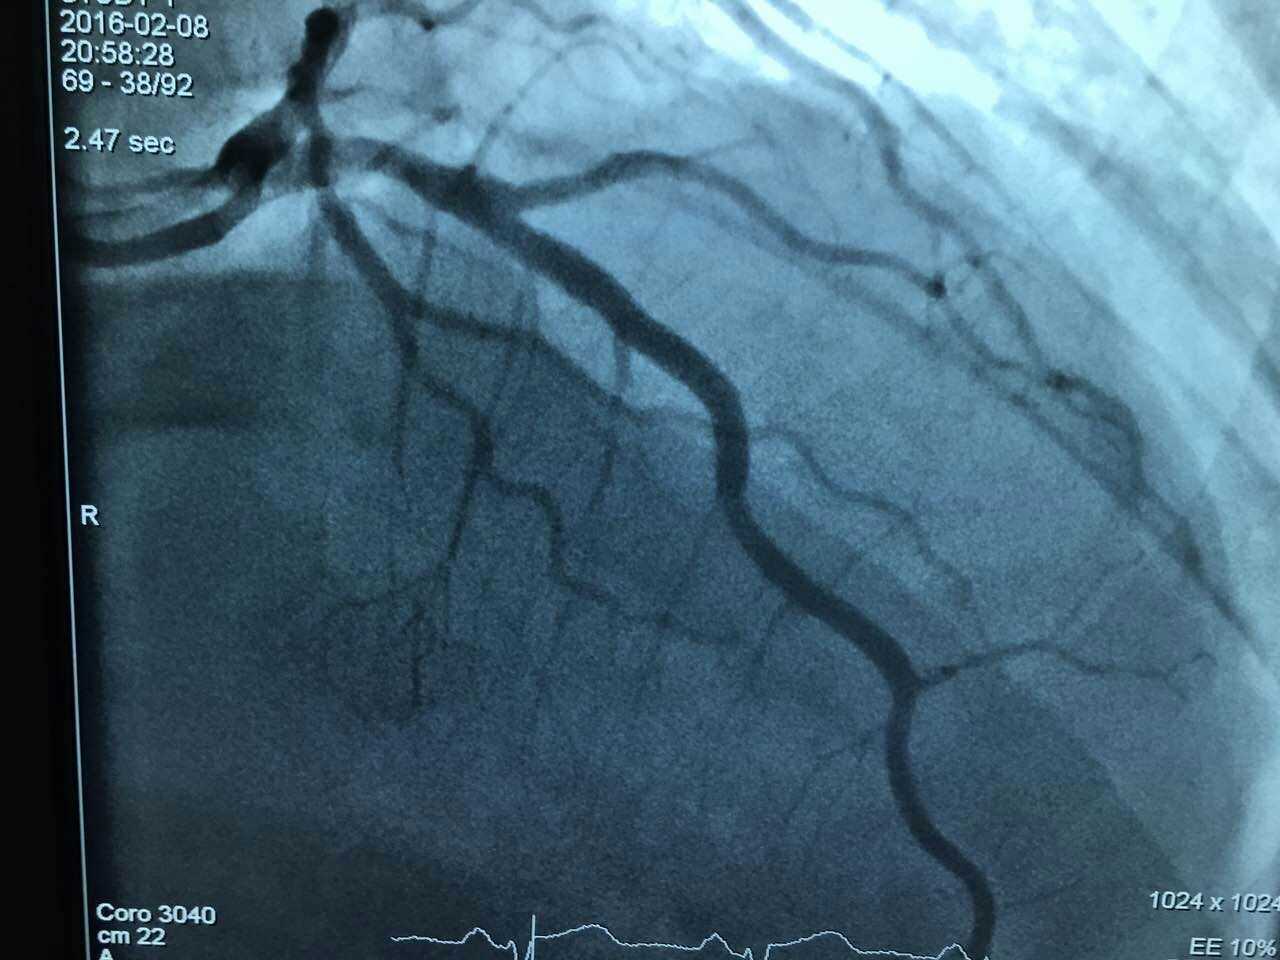

心脏内科专家王守力教授呼吁:谨防节日病,尤其是中青年。大年初一继凌晨抢救一例心梗患者,该团队又为一例中年患者AMI(急性心梗)进行了疏通手术,手术团队24小时待命状态。小编为他们点赞。